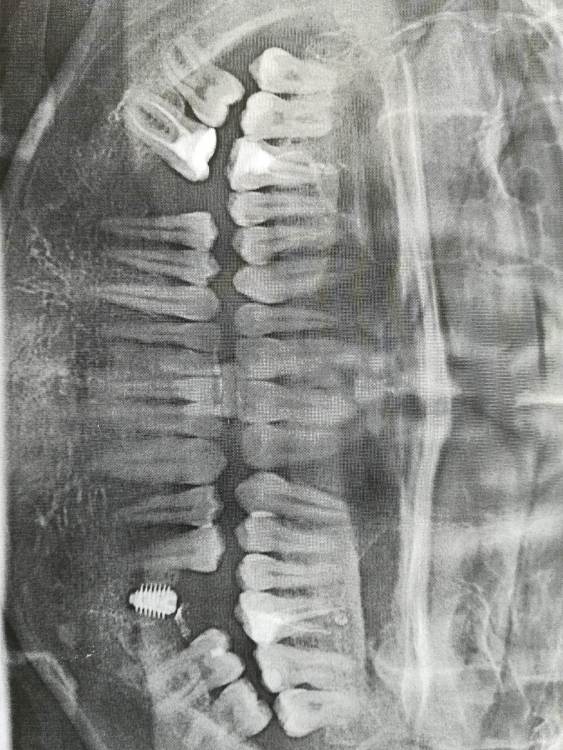

Nik-E Опубликовано 11 октября, 2021 Поделиться Опубликовано 11 октября, 2021 Здравствуйте. Нужно мнение специалистов. Была проведена имплантация, сделан снимок, на снимке непонятное пятно как будто похожее на резьбу, до установки импланта такого пятна не было. Что это за пятно может быть? И правильно ли установлен имплант? Заранее спасибо. На снимке я место с пятном выделил. Ссылка на комментарий